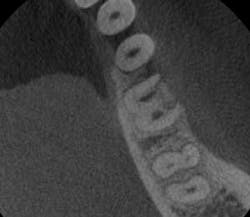

- This is another case of what could easily be misdiagnosed as internal resorption on tooth #No. 24. If you look closely in Figure 7, the outline of the canal can be seen.

- In Figure 8, the lesion is advanced significantly (one-and-a-half years had gone by) the irregular borders and moth-eaten appearance is easily observed.

- Definitive diagnosis: external resorption.